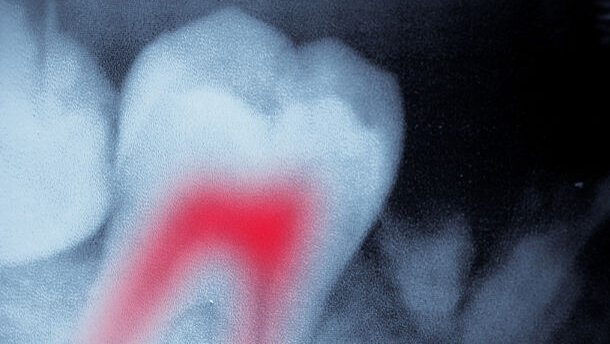

CHICAGO, Illinois & MIAMI, Floride, États-Unis : La douleur dentaire survenant après un traitement endodontique pourrait provenir le plus souvent d'une autre source que de la dent traitée elle-même. Ayant examiné les études sur une période de 60 ans, des chercheurs américains affirment que dans six cas sur dix de douleur post-traitement endodontique, la cause n'a rien à voir avec la dent qui a été traitée à l'origine.

Dans un rapport publié dans le numéro de décembre de The Journal of the American Dental Association, des chercheurs de l’école dentaire de l'Université du Minnesota ont analysé 10 des 770 études de langue anglaise menées entre 1949 et 2009. Pour que le cas soit sélectionné, il était nécessaire que les dents traitées aient été suivies pendant au moins six mois après le traitement.

Selon le rapport, les résultats pourraient avoir des conséquences graves pour le diagnostic et la gestion clinique de la douleur post-traitement endodontique. Le Dr Paul Benjamin, un dentiste de Miami, a déclaré dans un commentaire qui a été également publié par la revue que si les résultats étaient vérifiés, près de 700 000 cas de douleurs relatives aux dents pourraient être diagnostiqués à tort sur une base annuelle dans les seuls États-Unis. Il a conseillé aux cliniciens d'intégrer dans leurs diagnostics futurs les nouvelles connaissances de la douleur post-traitement endodontique et d’éliminer les autres sources possibles, y compris les douleurs associées à l'appareil locomoteur ou à des maladies systématisées comme le cancer.

Dans les dernières études, on a identifié une douleur post-traitement endodontique pour 5 à 6 pour cent de toutes les dents ayant subi un traitement endodontique. La prise en charge clinique est généralement axée sur la dent traitée elle-même et comprend l'administration de médicaments anti-douleur.